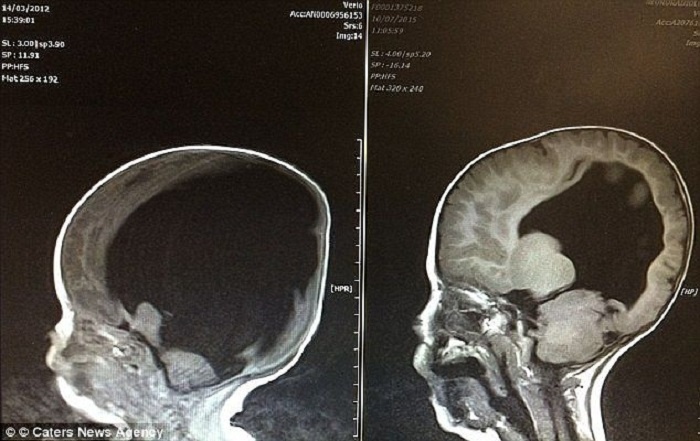

Страшные снимки не напугали родителей: они решили оставить ребенка (фото при рождении и через несколько лет).

То, что произошло с мозгом Ноя ещё в утробе матери, медики объяснили позднее. Из-за порэнцефальной кисты, заполненной спинномозговой жидкостью, ткани мозга начали разрушаться. У мальчика также обнаружили расщепление позвоночника и гидроцефалию — именно из-за этого его голова казалась непропорционально большой, а кости черепа — будто бы разошедшимися.

Позднее выяснилось: возможно, большая часть мозга не была разрушена, а просто оказалась сдавленной изнутри. Это открытие стало переломным. С каждым годом мозг Ноя начал восстанавливаться и в итоге достиг почти 80 процентов от нормального объёма. Для врачей это стало настоящим потрясением: они не могли поверить, что ребёнок, которого некогда называли «растением», научился говорить, читать, писать и считать.